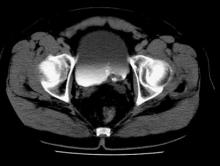

The patient was referred to Urology and a cystoscopy showed a bladder tumor; complete endoscopic resection confirmed transitional cell carcinoma (TCC).

A metastatic workup for TCC includes a complete blood count, blood chemistry tests (including alkaline phosphatase tests), liver function tests, and a CT or magnetic resonance imaging (MRI) scan of the chest and abdomen. A bone scan is indicated in patients with bone pain and/or elevated levels of serum alkaline phosphatase.

In this case, the patient had a low-grade tumor and no evidence of metastasis. Thus, he was treated with resection alone and close follow-up by Urology.